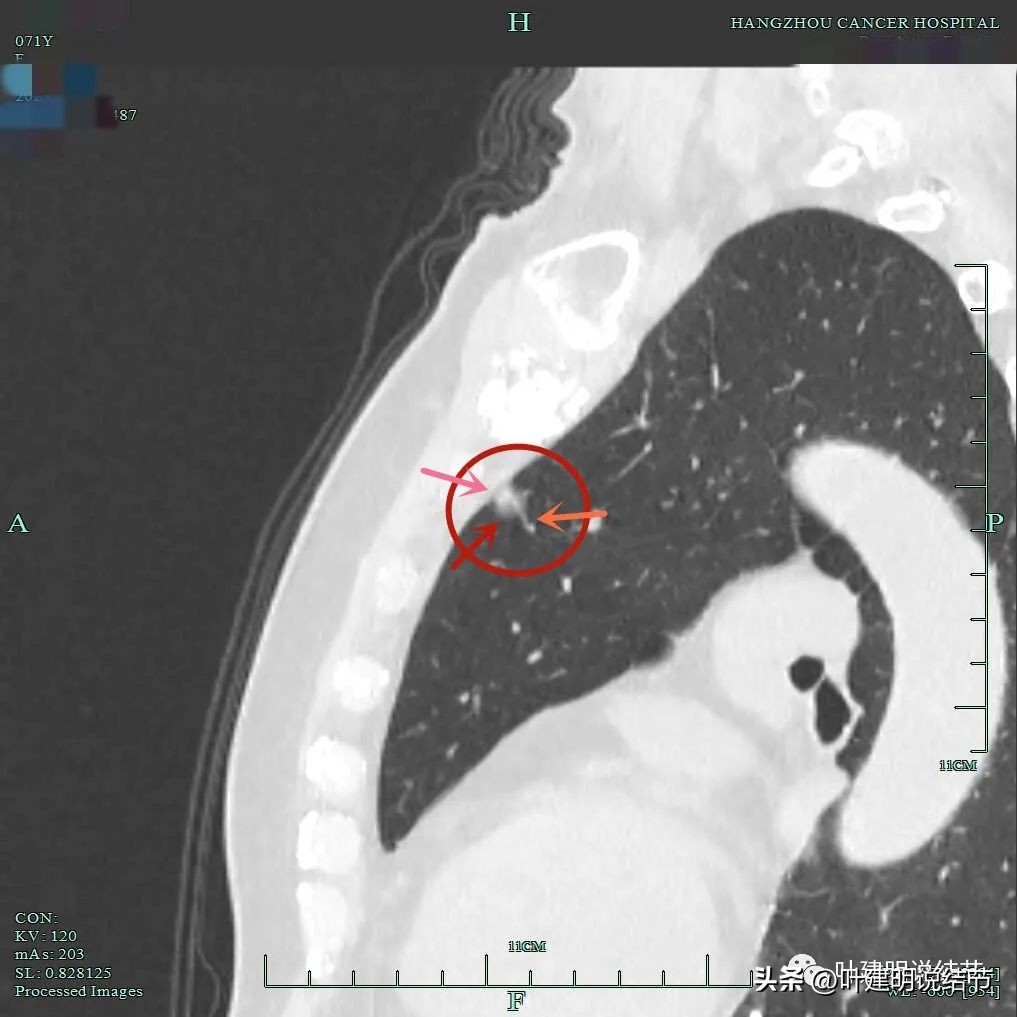

靶扫描显示主病灶混合磨玻璃密度,边缘实性成分(粉色箭头);瘤肺边界清(红色箭头);部分边缘似有毛刺(紫色箭头)。

灶内实性成分(粉色箭头)以及微血管进入(桔色箭头);整体密度不均,轮廓与瘤肺边界清(红色箭头)。

血管进入,混合密度,轮廓清。